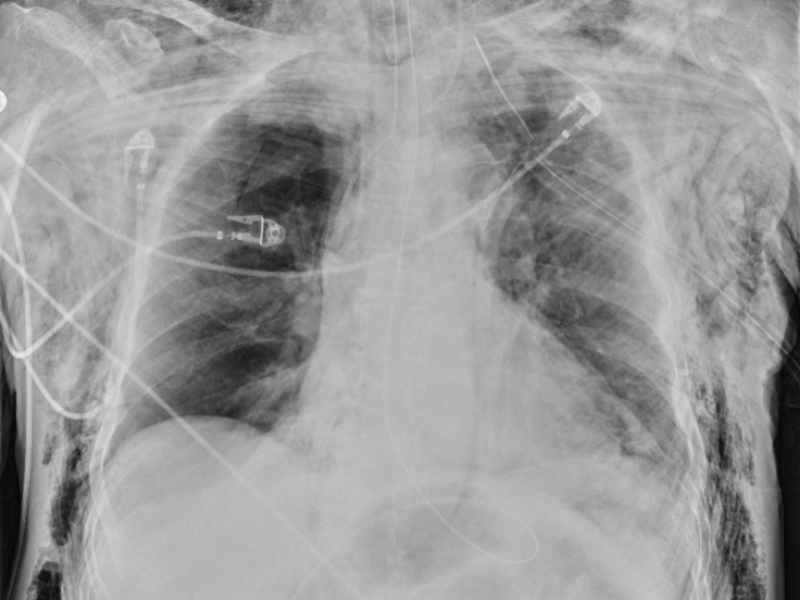

A 55 year old male presents to the ED in respiratory